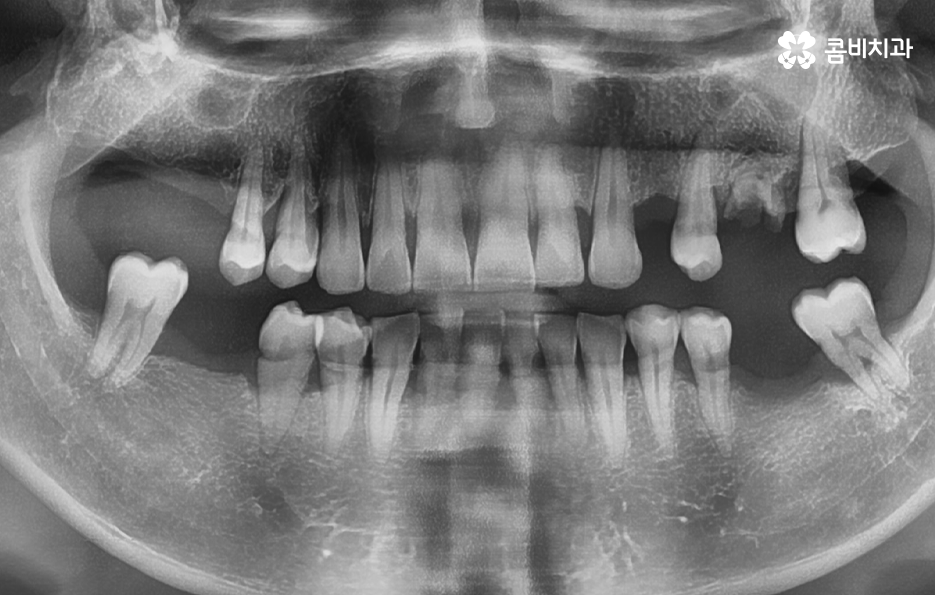

이번 포스팅에서는 그렇다면 왜 50대에서 60대에 넘어가는 시점에 치아를 상실하는 분들이 크게 늘어나는지 그 이유를 알아볼 거예요. 사람의 치아는 윗니와 아랫니를 모두 합하면 28개의 치아를 갖고 있으며 질병관리청 국민건강 통계에 의하면 한국 50대 성인의 평균 잔존 치아 개수는 25.5개, 60대는 22.8개, 70대 이상은 다시 16.2개로 평균 잔존 치아 개수의 감소폭이 50대 부터 점점 크게 줄어드는 것을 확인할 수 있어요

위 사진을 보시면 치아 자체의 노화나 균열도 물론 크지만 잇몸이 내려앉아서 치아의 뿌리 부분이 외부에 노출되어 있는 것을 알 수 있는데요. 노인임플란트 필요로 하는 분들의 치아 상실의 대표적 원인은 충치 부터 오래된 크라운, 치아의 손상 및 균열로 인한 문제도 크겠지만 결정적으로는 치주염으로 인해 잇몸 뼈가 녹고 잇몸 퇴축으로 인한 치아 상실이 노년기에 발생하는 치아 상실의 대표적 원인이 되고 있어요

위 케이스의 노인임플란트 치료의 경우 치아의 균열부터 뿌리까지 깊어진 충치, 치주염 까지 복합적인 이유로 치아를 상실하고 여러 개의 임플란트를 식립한 사례라고 할 수 있는데요. 그래도 아직은 잔존하고 있는 치아가 많기 때문에 이미 상실한 치아에는 노인임플란트 각 위치에 맞게 적절한 치료를 받고 나머지의 자연치아에 대해서는 잘 관리하는 것이 중요한 시점이라 할 수 있어요